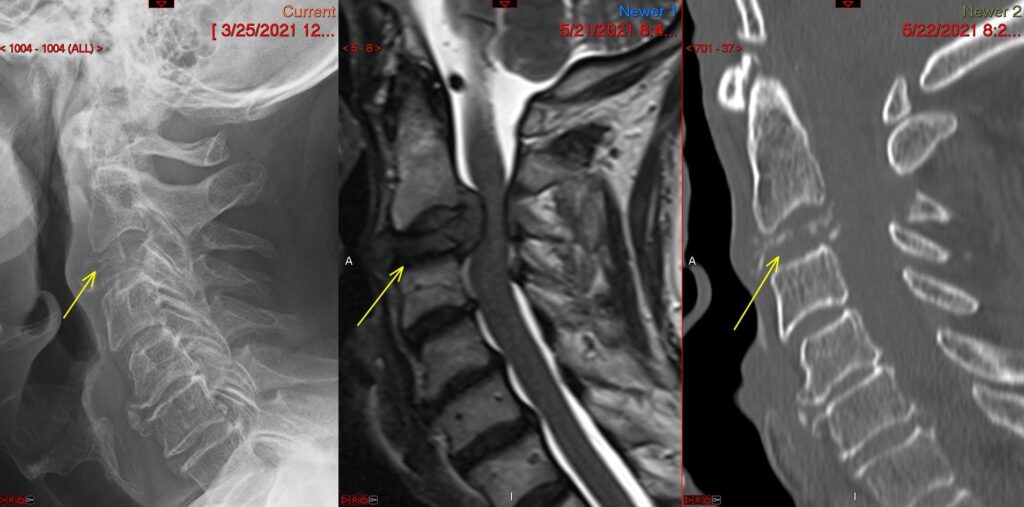

ACCF Preop 1024x507

Anterior Cervical Corpectomy and Fusion

c5 corpectomy ct

c5 corpectomy

anterior cervical c5 corpectomy and fusion